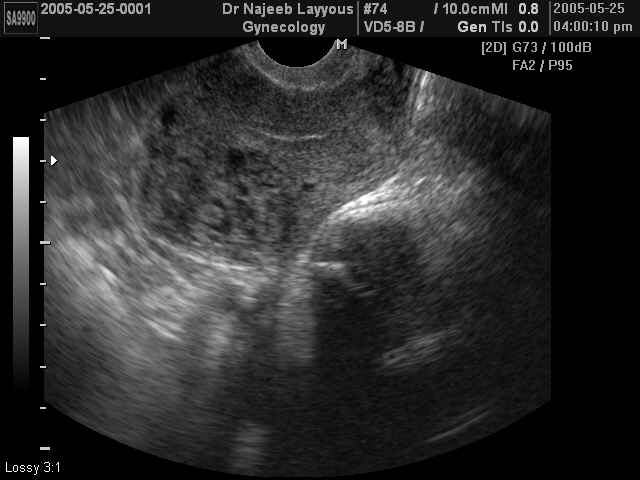

صور طبية للحمل بجهاز الالتراساوند | الدكتور نجيب ليوس